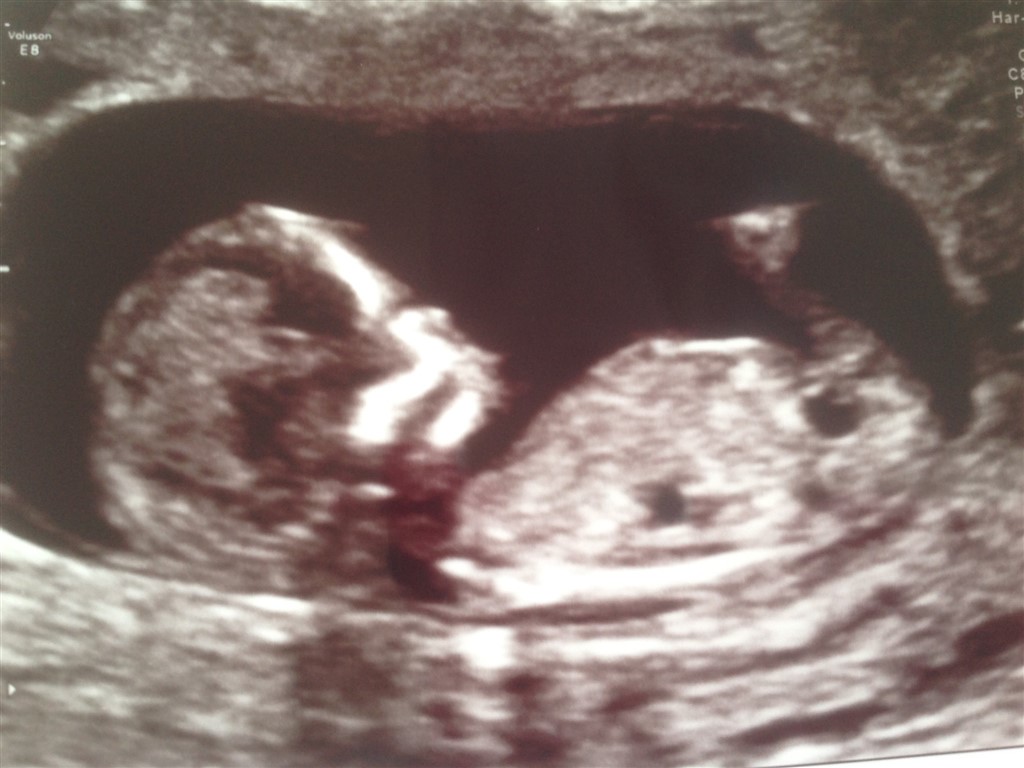

Hej alle, jeg har lige været til scanning (NF). Damen der scannede mig kunne sagtens se kønnet, men hun vil ikke fortælle os det, da hun nok ikke er 100% sikker, men kan i se kønnet? Jeg ved overhovedet ikke om man kan se det, på de billeder her, men kunne være fedt hvis i vil smide et gæt

P.S baby var sund og rask

uge 13+0